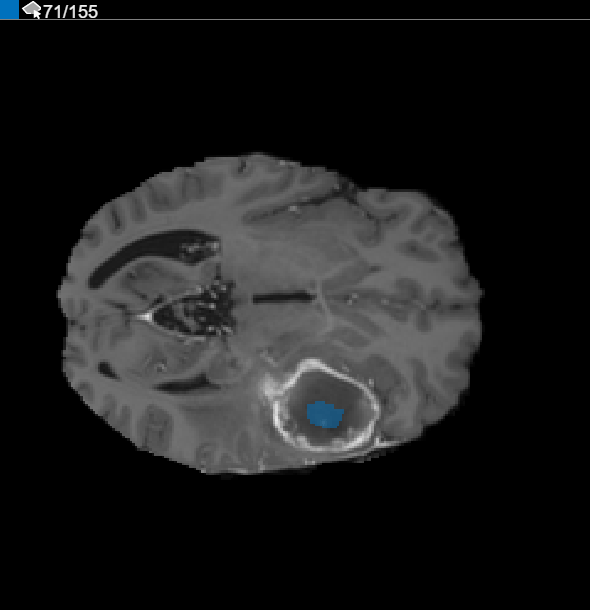

内挿の使用後、個々のスライスをチェックして、満足できる ROI が作成されているかを確認します。スライス 71 では、セグメント化するオブジェクト全体が ROI で塗りつぶされていないことに注目してください。[ペイント ブラシ] ツールを使用することで、ROI を手動で調整できます。あるいは、[自動化] タブのツールのいずれかを使用することもできます。たとえば、[動的輪郭] を使用して、腫瘍の全体が塗りつぶされていないスライスで ROI を大きくすることができます。また、[アルゴリズムの追加] を使用して、ROI 上で動作する独自のアルゴリズムを指定することもできます。